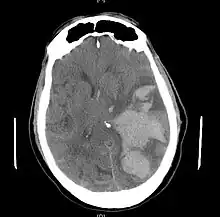

a-c)CT scan images after clinical signs of brain herniation developed

Types of brain herniation.[6]